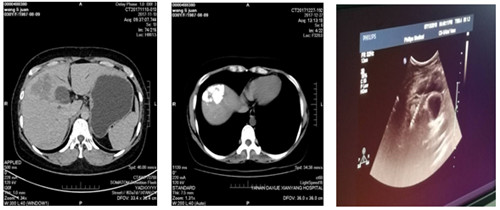

2018年5月前我院腫瘤胸外科收入一年輕女性患者,檢查確診為肝癌,經(jīng)腫瘤多學(xué)科會(huì)診后,行多次肝動(dòng)脈灌注化療栓塞術(shù),治療過程順利,現(xiàn)復(fù)查CT示碘油沉積區(qū)域面積較前減小。為使病人得到最佳治療,在我院腫瘤病院張海濤院長(zhǎng)主持下,召開了腫瘤多學(xué)科會(huì)診MDT,經(jīng)過充分的討論,制定了嚴(yán)謹(jǐn)?shù)闹委煼桨?,確立現(xiàn)在的最佳治療方法為無痛肝癌射頻消融術(shù)。

在腫瘤胸外科苗滿園主任帶領(lǐng)下,由腫瘤外科、超聲科及手術(shù)麻醉科組成的肝腫瘤微創(chuàng)治療團(tuán)隊(duì),在鎮(zhèn)痛麻醉后超聲引導(dǎo)下將電極準(zhǔn)確插入肝腫瘤內(nèi)部,采用雙針電極對(duì)肝腫瘤進(jìn)行射頻消融手術(shù)。整個(gè)手術(shù)過程約40分鐘,達(dá)到了預(yù)期滿意效果及消融范圍。術(shù)后患者有輕微不適,無出血及鄰近臟器損傷。